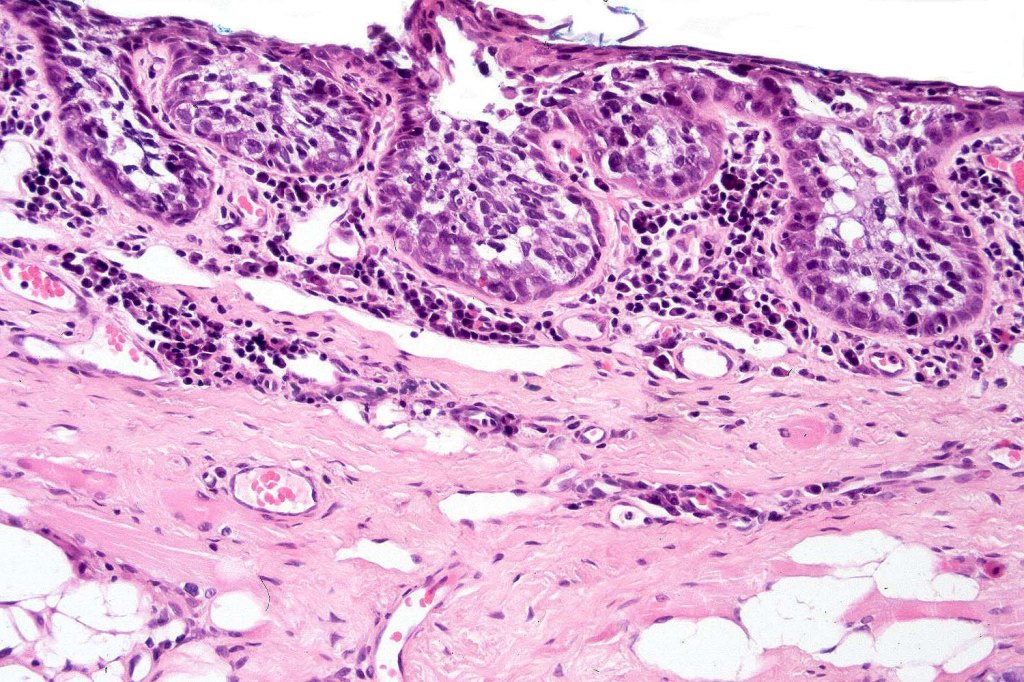

•May be associated with Pagetoid spread

•Periocular shave biopsies can be misleading and easily mistaken for Bowen’s disease

•Tumors are composed of an admixture of darkly staining basaloid cells with hyperchromatic or vesicular nuclei and more obvious sebaceous cells with eosinophilic, bubbly, multivacuolated cytoplasm frequently indenting the nucleus (scalloped)